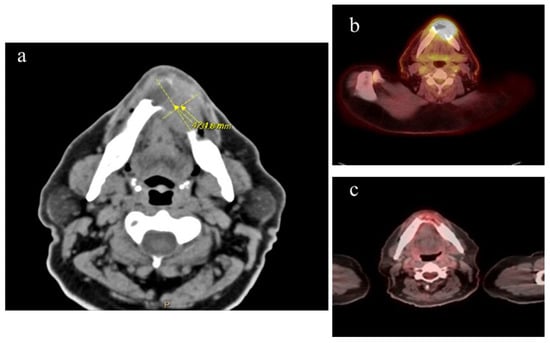

Staging confirmed that he had stage IE CD30+ DLBCL with soft tissue/mandible involvement and an IPI of 1 (Figure 1). Chemotherapy was initiated with rituximab, brentuximab vedotin, cyclophosphamide, vincristine, and prednisone. He was in complete remission after three cycles of chemotherapy followed by consolidative radiation treatment.

Figure 1. A 64-year-old M with DLBCL stage IE. (a) CT imaging of mandible with mass and associated bone destruction at the time the lymphoma diagnosis was made, 9 months after initial presentation with loose teeth and shortly after completing a 6-week course of oral antibiotics. (b) PET scan taken during initial lymphoma staging, with uptake in mandibular area SUV 18.8. (c) PET scan after completion of 3 cycles of chemotherapy, showing complete remission.